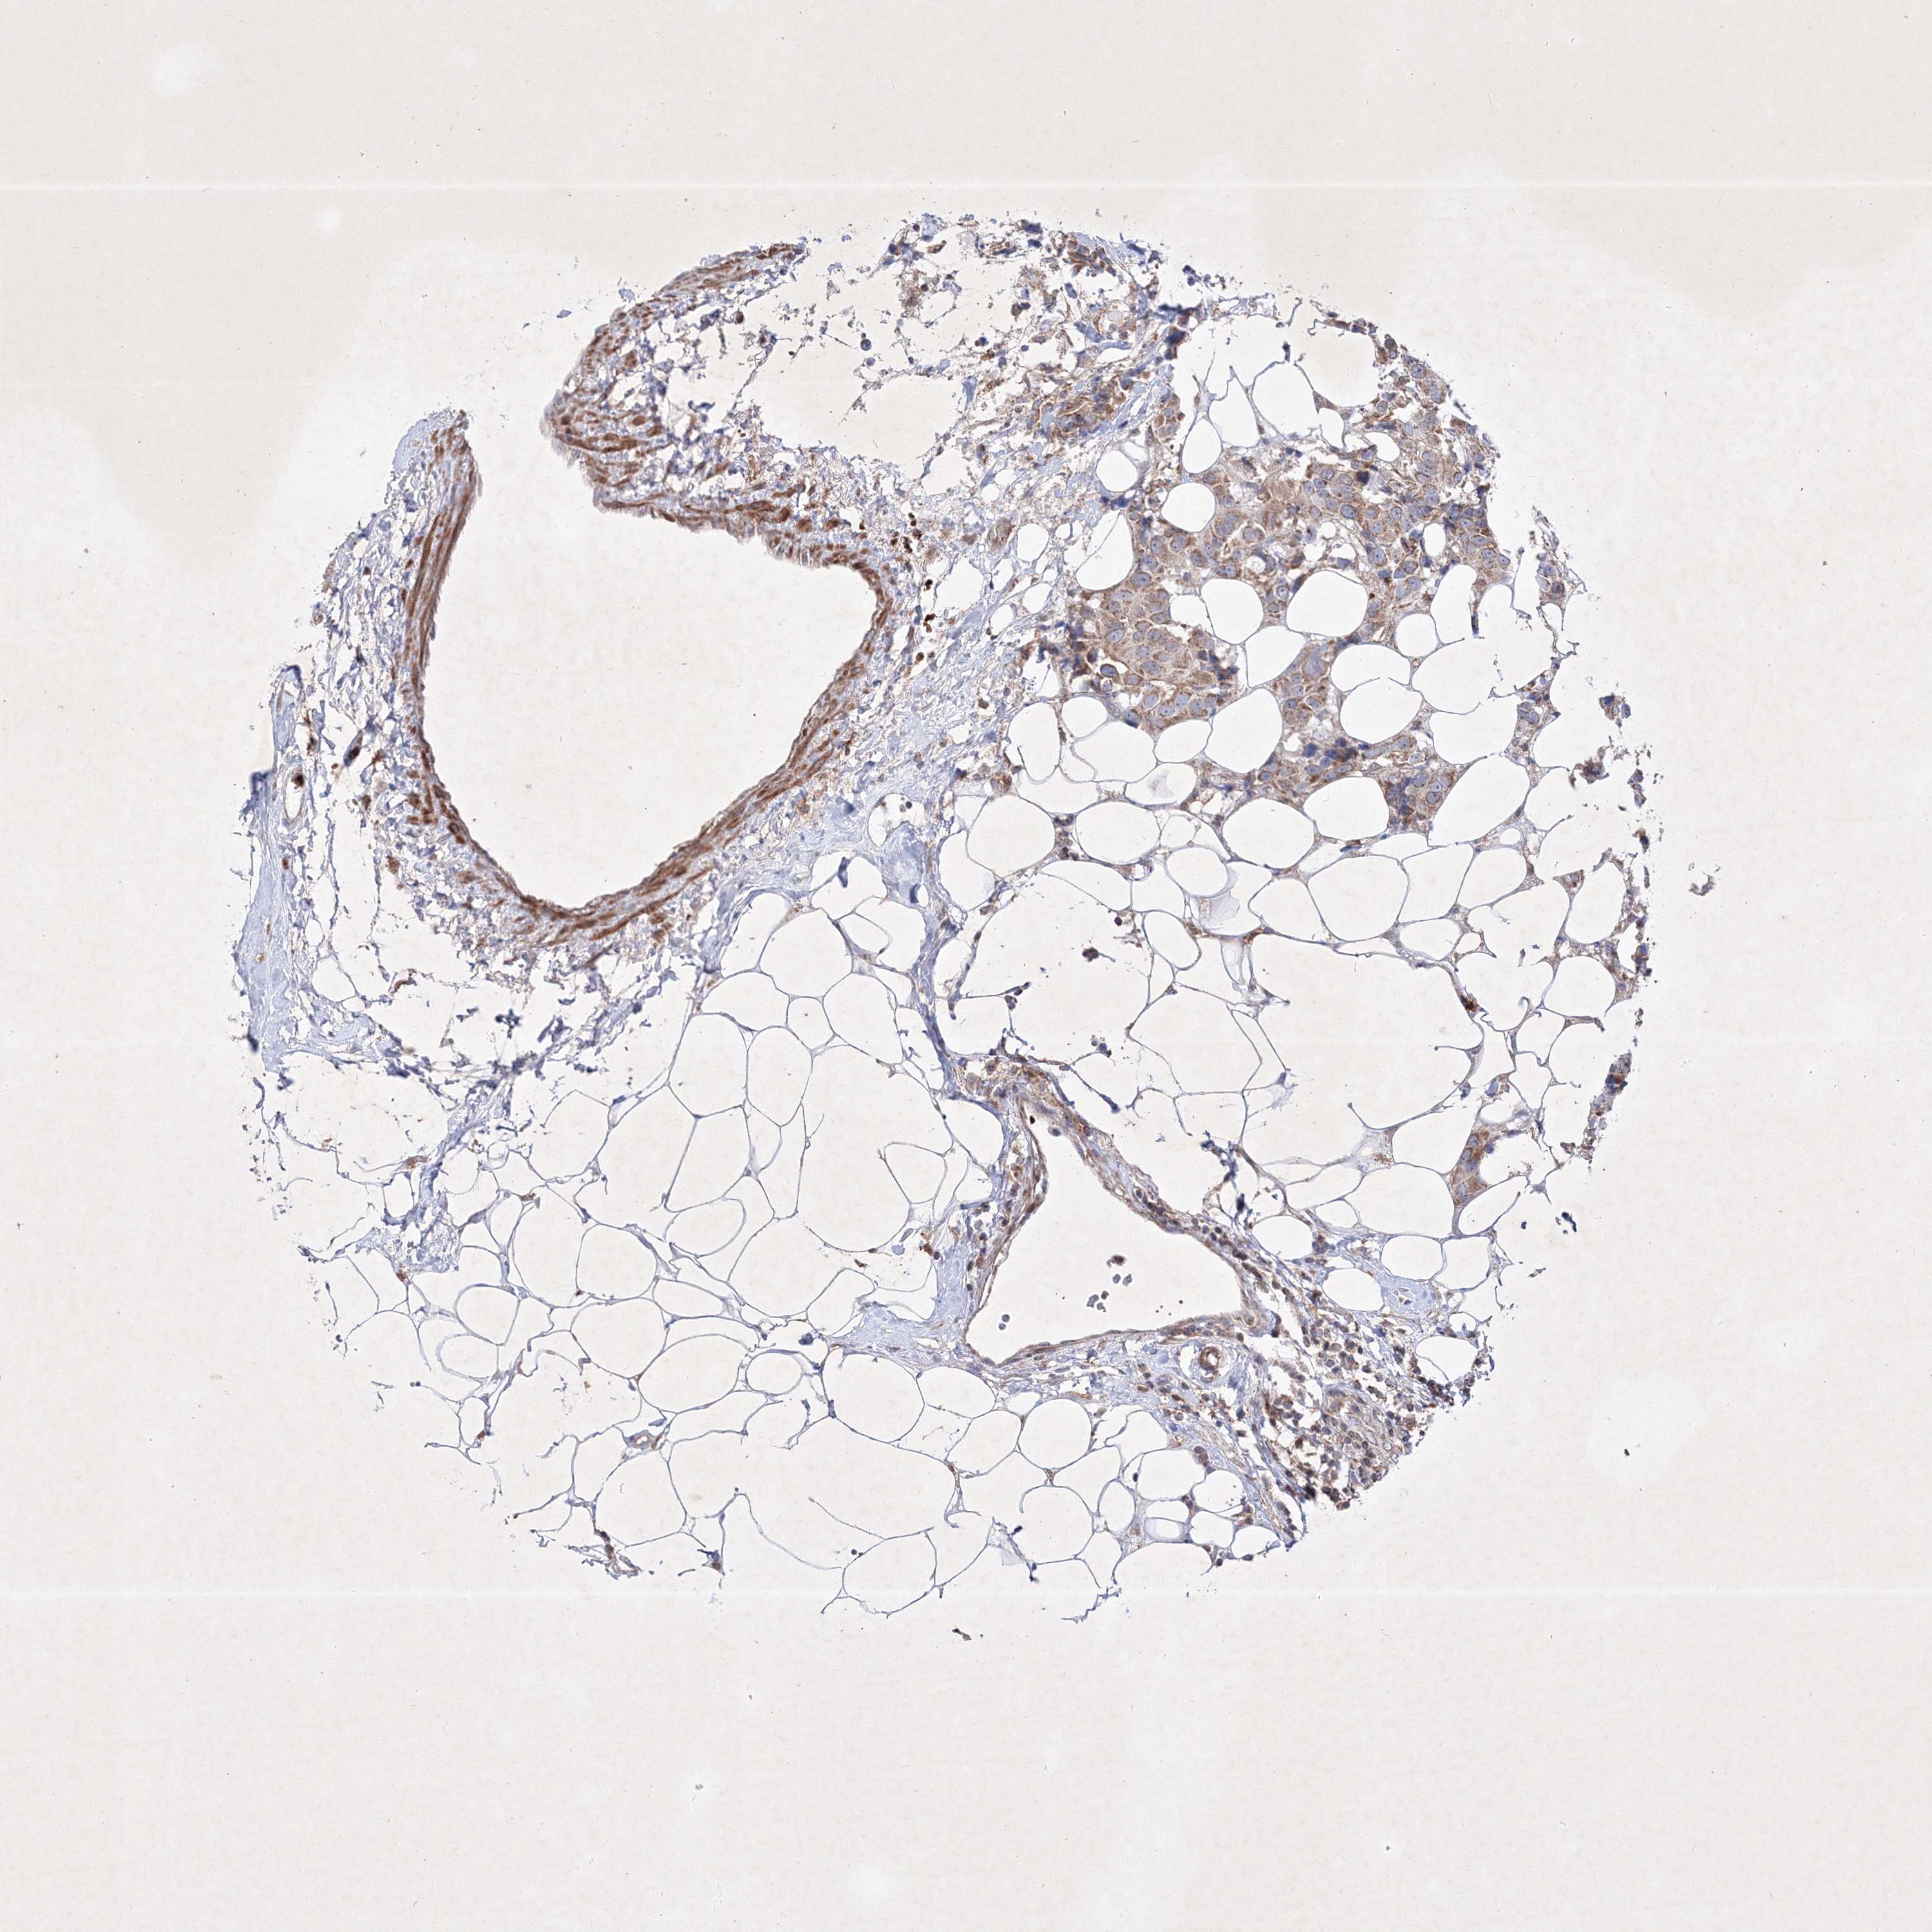

CANCER BREAST CANCER Show tissue menu

BRCA TCGA BRCA VALIDATION PROTEIN EXPRESSION